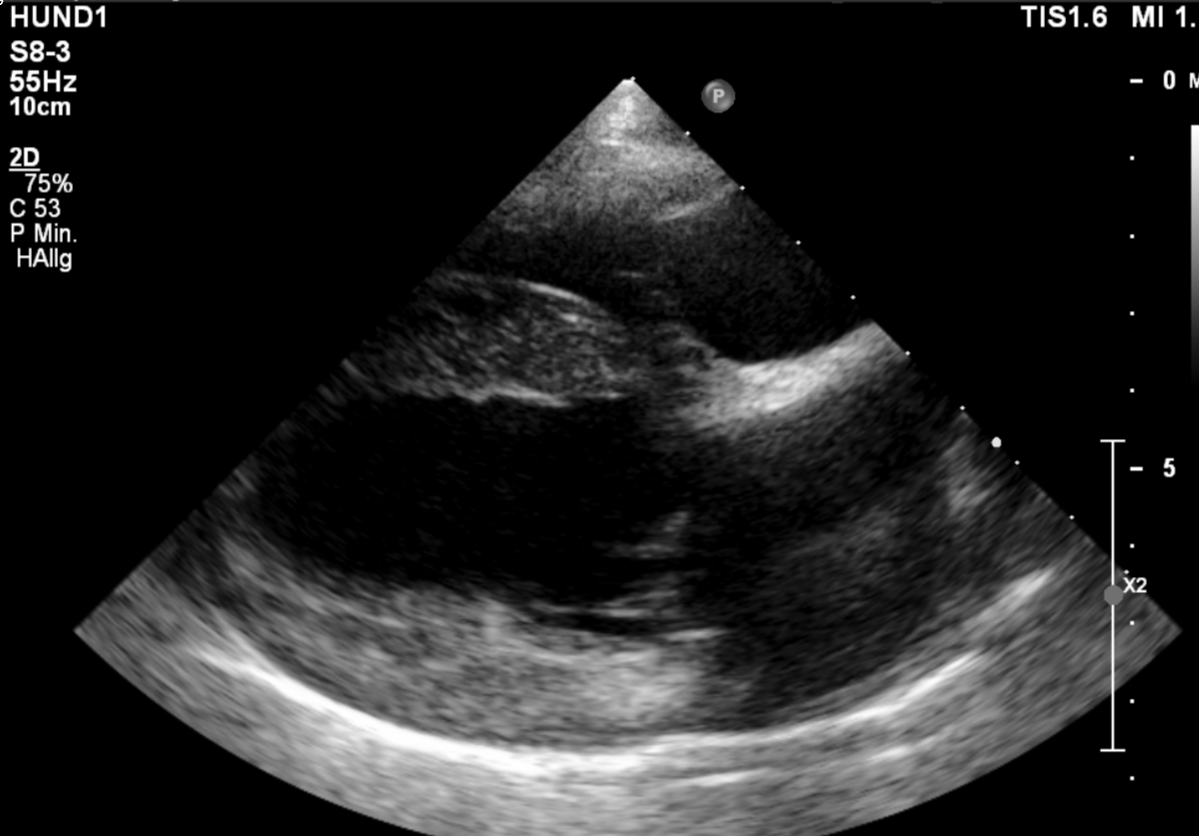

Ab einem gewissen Alter sollte daher ein regelmäßiger Check-up des Herzens obligatorisch sein. Neben dem Doppler- und B-Mode- Herzultraschall, gehören das EKG, das Röntgen zum manchmal auch Blutuntersuchungen zur vollständigen Abklärung der Herzgesundheit dazu. Frau Dr. Theresa Eulitz (Zusatzbezeichnung Kardiologie) ist unsere Spezialistin in Herzensangelegenheiten.